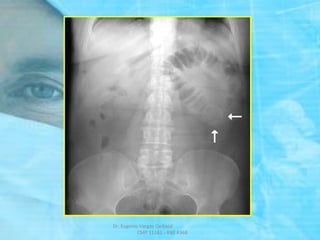

RADIOGRAFIA SIMPLE DE ABDOMEN

DE PIE Y DECUBITO

 Mejor valor diagnóstico.

 Se debe tomar en posición DE PIE

y DECUBITO, incluir diafragma

y pelvis.

 Rx. de PIE: NHA.

 Rx. de DECUBITO:

Gas Intraintestinal

ASAS YEYUNALES:

SIGNO

“PILA DE MONEDAS”